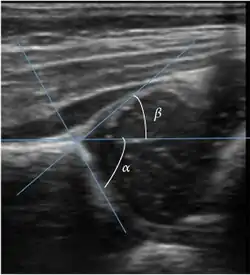

Ultrasound

Ultrasound is the first-choice technique for diagnosis of newborns hip dysplasia. In experienced hands with appropriate technology, ultrasound can also be useful during the first year of life. Some European healthcare systems encourage universal ultrasound screening in neonates between the sixth and eighth weeks. Although it shows higher initial costs caused, it leads to significant reduction in the total number and overall costs of dysplastic hips undergoing operative and nonoperative treatment.[1]

Ultrasound allows categorizing pediatric hips, according to Graf’s criteria, in four main types: normal, immature, and dysplastic (subluxed and dislocated). This classification is based on measurements of the acetabular inclination angle (alpha), cartilage roof angle (beta), and infant age. The femoral head coverage can also be determined by dividing the length of the femoral head covered by the acetabular fossa and the diameter of the femoral head. Its lower normal limits are 47% for boys and 44% for girls (Figure 11).[1]

Figure 11:

Useful ultrasound measures in neonatal hip sonography, alpha and beta angles.[1] -

Measurement of femoral head coverage.[1]